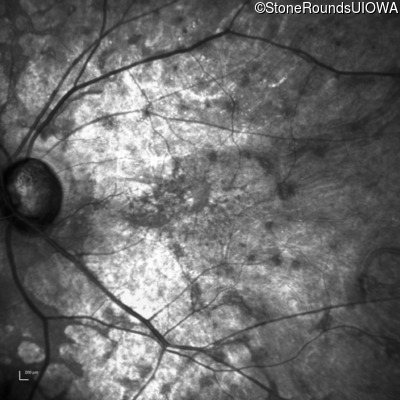

Infrared Fundus Photograph - Right - 20/25 -1

Exemplar